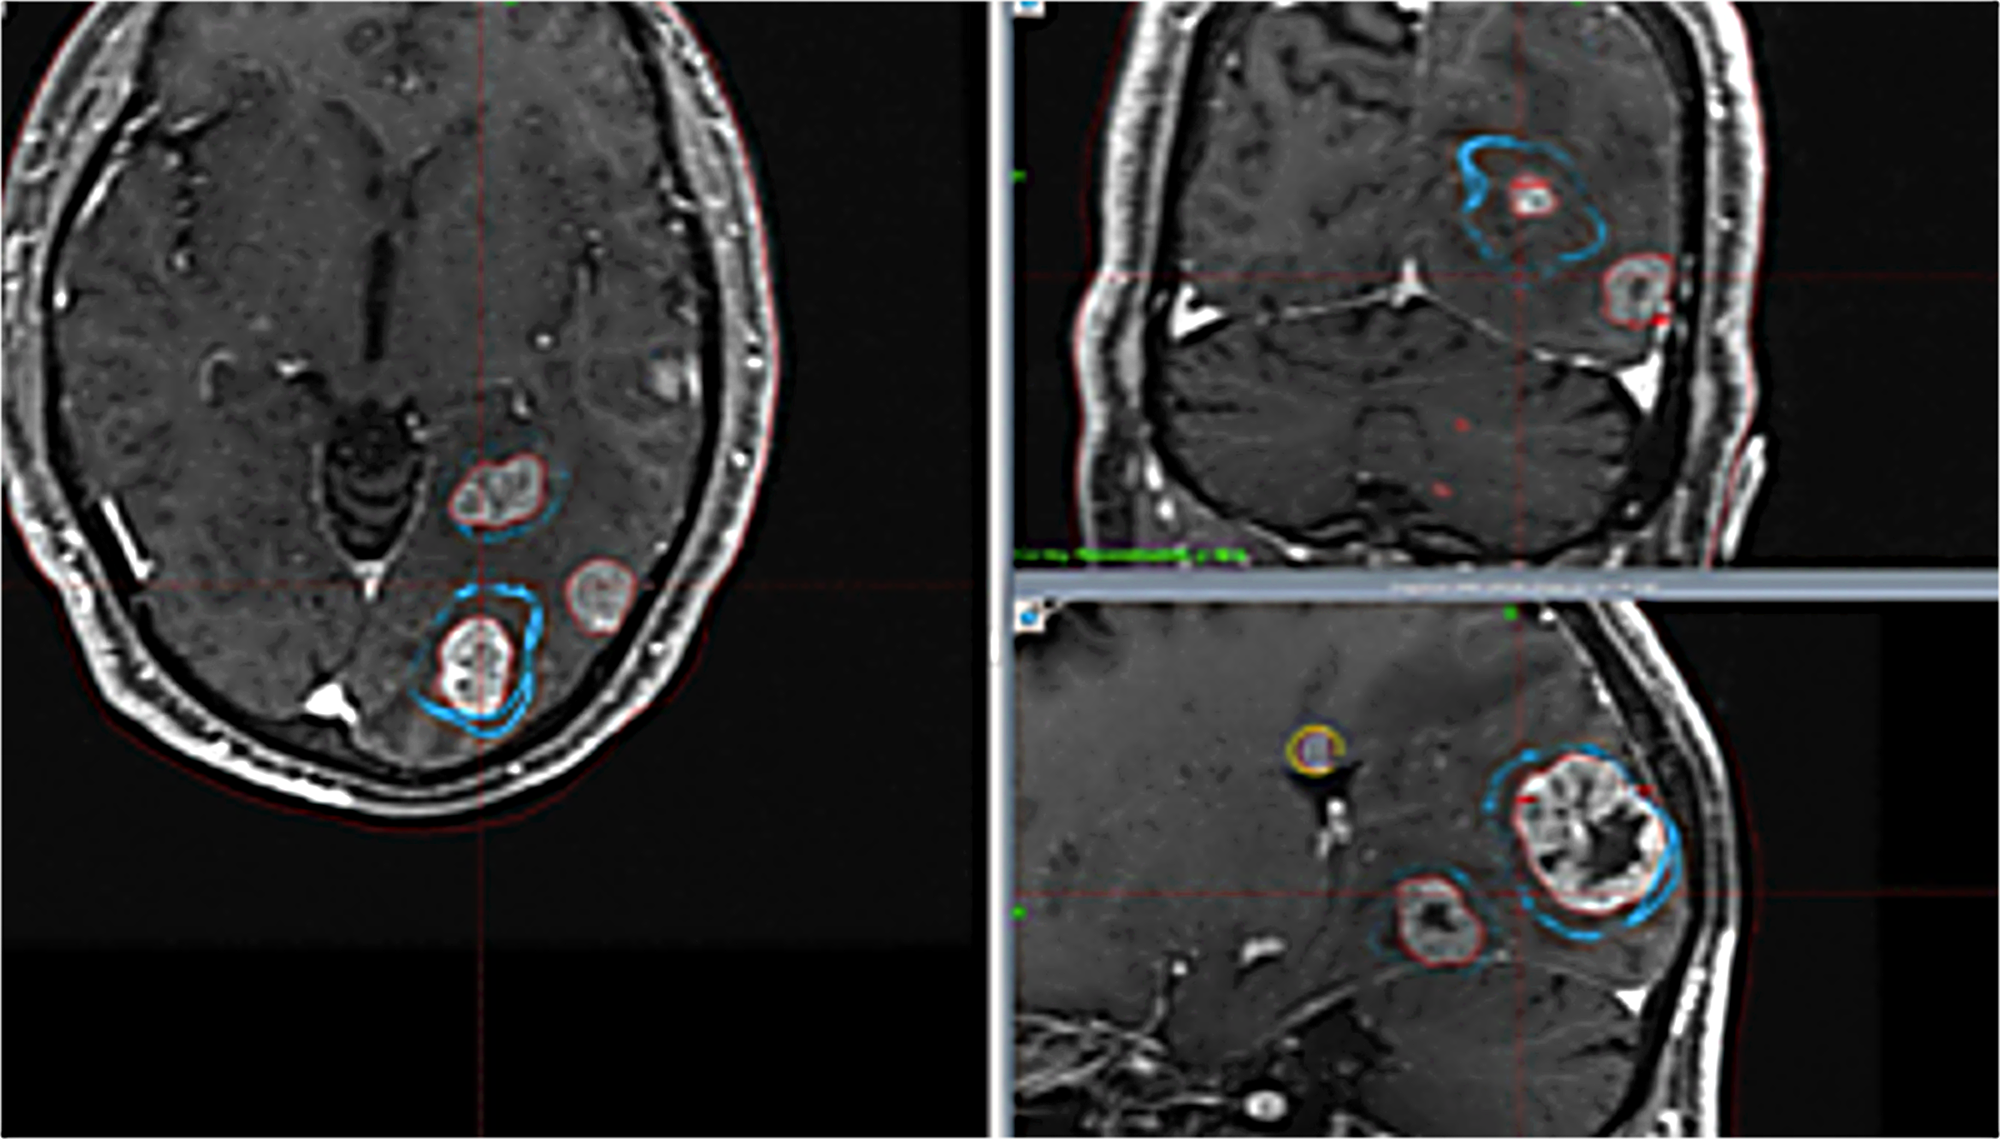

Cureus SingleIsocenter Volumetric Modulated Arc Therapy (VMAT Radiosurgery Brain Lesions Stereotactic radiosurgery is a method of delivering radiation to brain tumors. Stereotactic radiosurgery is a very precise form of therapeutic radiation that can be used to treat abnormalities in the brain and spine, including cancer, epilepsy, trigeminal neuralgia and. Stereotactic radiosurgery targets brain abnormalities or the area of your brain that shows symptoms. There are different types of technology used. Radiosurgery Brain Lesions.